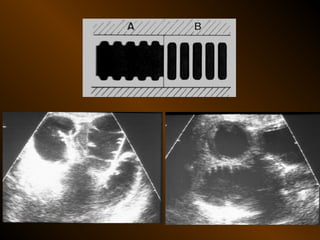

PHÂN BIỆT

RUỘT NON – ĐẠI TRÀNG

• Các nếp Kerckring

• Nếp ngấn thanh mạc

• Khẩu kính

• Số lượng quai

• Phân bố các quai ruột

• Cao / rộng

• Chất cặn bã